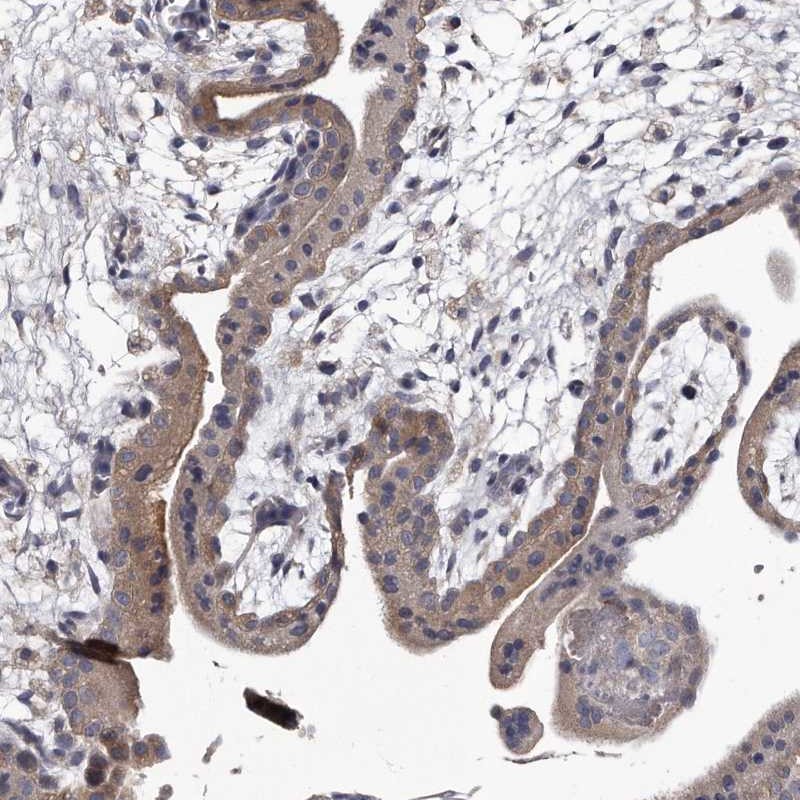

Immunohistochemical staining of human placenta shows cytoplasmic positivity in trophoblastic cells.